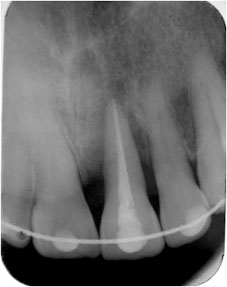

L’examen clinique et radiologique montre que la patiente présente une parodontite chronique généralisé (AAP, 1999) (fig 1 et 2).

Le cliché rétro alvéolaire met en évidence deux zones radioclaires coniques opposées par leur sommets : la lésion parodontale a un sommet en apical, alors que la lésion endodontique a un sommet cervical (3).

La continuité entre la poche parodontale et la lésion d’origine endodontique peut être individualisée grâce à une radiographie rétro alvéolaire cône de gutta en place.

Image en deux cônes opposés par leur sommets en place montre une communication endo parodontale (fig 4) |